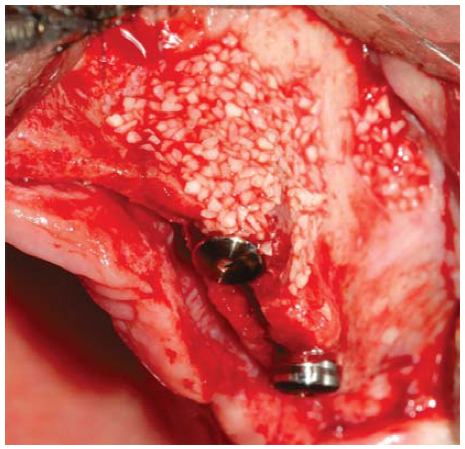

Para esta cirugía, el paciente recibió la misma preparación prequirúrgica que se utilizó para el maxilar superior. Se inició con una incisión intrasulcular a nivel de todas las piezas dentarias y se elevó el colgajo mucoperióstico. Luego se realizó la remoción de las piezas dentarias y tejido de granulación adyacente, tratando de preservar todo el remanente óseo posible. A continuación, se realizó la regularización y remodelado del reborde óseo utilizando fresas multilaminadas con abundante irrigación. Seguidamente, se inician las perforaciones en los sitios designados para la colocación de los implantes con una secuencia de fresado convencional. Posteriormente, se colocaron los cuatro implantes ubicando sus plataformas protésicas a un mismo nivel. Debido a la presencia de defectos óseos de dos y tres paredes alrededor de los implantes, se colocó en estos un injerto óseo bovino particulado (Bonefill® Bionnovation Biomedical, Sao Paulo-Brazil). Finalmente, se suturó con nylon monofilamento 5/0.